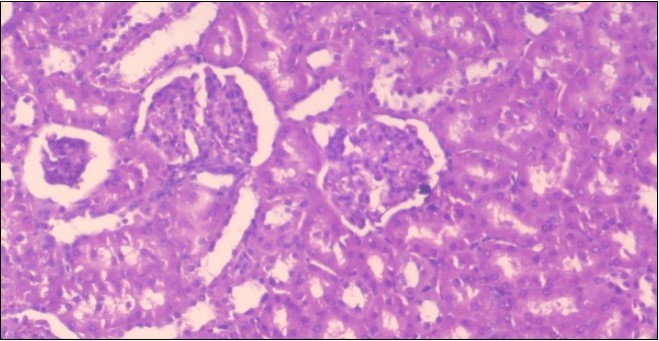

The histological examination of the kidney of the control rats fed on a standard diet showing normal rounded capsules with normal Bowman's glomeruli, round proximal tubules and elongated distal tubules with high cuboidal cells figure 1. The rats fed (HFD) showed fatty degeneration of the tubules with eosinophilic material deposition, glomerular atrophy with wide urinary space and distal tubules with extrusion of nuclei into lumen figure 2. By comparison kidneys of rats which were treated by fennel after being obese and the control rats observed partial improvement in both Bowman's capsules and proximal tubules. Note the distal tubules show less focal fatty infiltration figure 3.While examination of rats kidney that were treated by ator after obesity showed improvement in Bowman's capsules with normal glomerular and partial improvement in proximal tubules and distal tubules, figure 4. Kidney of rats that were treated by fennel and ator after obesity and the control rats showed high improvement in the tissues with normal glomerular and that Most of Bowman's capsules and renal tubules, restoring their normal appearance figure 5.

Figure 2.Photomicrogragh of kidney section of obese rat showing fatty degeneration of the tubules with eosinophilic matrial deposition, glomrerular atrophy with wide urinary space and distal tubules with extrusion of nuclei into lumen , (H&E) (40X).